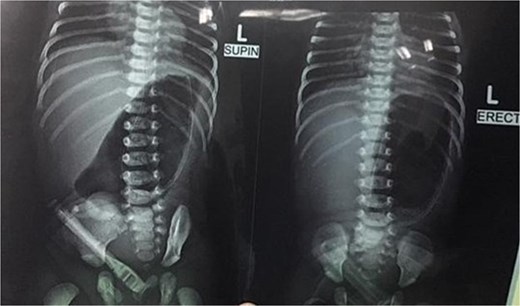

Initial management included nil per oral, fluid resuscitation, and nasogastric tube insertion. Laboratory investigations were unremarkable. Plain abdominal radiography revealed a single gastric air bubble with no distal gas, consistent with gastric outlet obstruction (Fig. 1). An upper gastrointestinal contrast study confirmed pyloric obstruction, with no contrast passing into the duodenum (Fig. 2).

The diagnosis of PA is typically confirmed postnatally based on clinical presentation, radiographic findings, and intraoperative exploration. Non-bilious vomiting, abdominal distension, and failure to pass stool are common clinical features, as seen in our patient [8]. Plain abdominal radiography often reveals a single gastric air bubble with no distal gas, while contrast studies demonstrate failure of contrast to pass beyond the pylorus, as observed in our case [9]. These findings are consistent with gastric outlet obstruction, which is pathognomonic for PA.